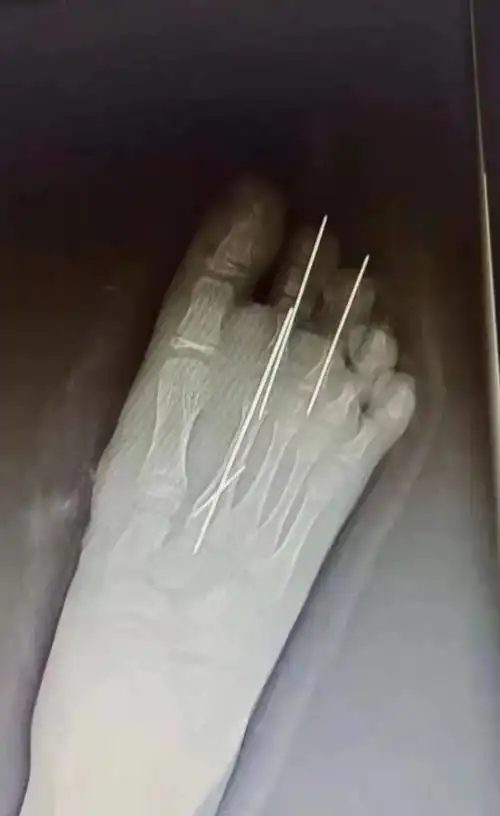

足踇趾撕脱离断伤

【讨论】足踇趾完全离断再植 [精华] [病例帖]